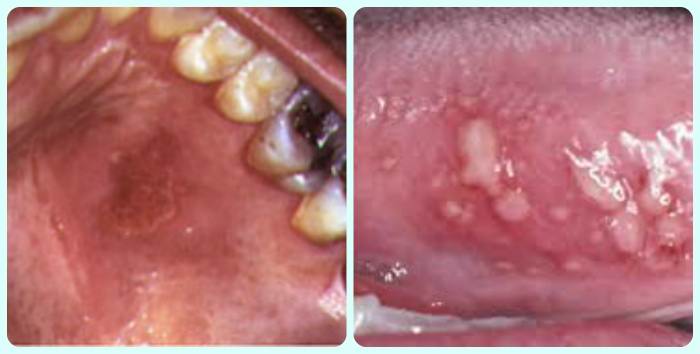

герпес на слизистой рта фото

герпес во рту фото

При герпесном стоматите в начале заболевания образуются пузырьки, которые располагаются обычно на деснах и тканях, прилегающих к костям.

Герпес может возникать на слизистой щеки, на языке, миндалинах, деснах – в любом месте ротовой полости.

5. Пузырьки могут быть разного размера и формы, они разрастаются и объединяются. Жидкость в них сначала прозрачная, через несколько дней она мутнеет, оболочка лопается.

6. На месте болячки образуется язвочка в белом налете, которая долго не заживает.

Как выглядит герпес во рту?

Первичная инфекция герпесом в полости рта. Проявляется в виде пузырьков с прозрачной жидкостью, которые затем разрушаются и образуют язвы, эрозии. Сопровождаются болями и высокой температурой, зудом и дискомфортом в области высыпаний.